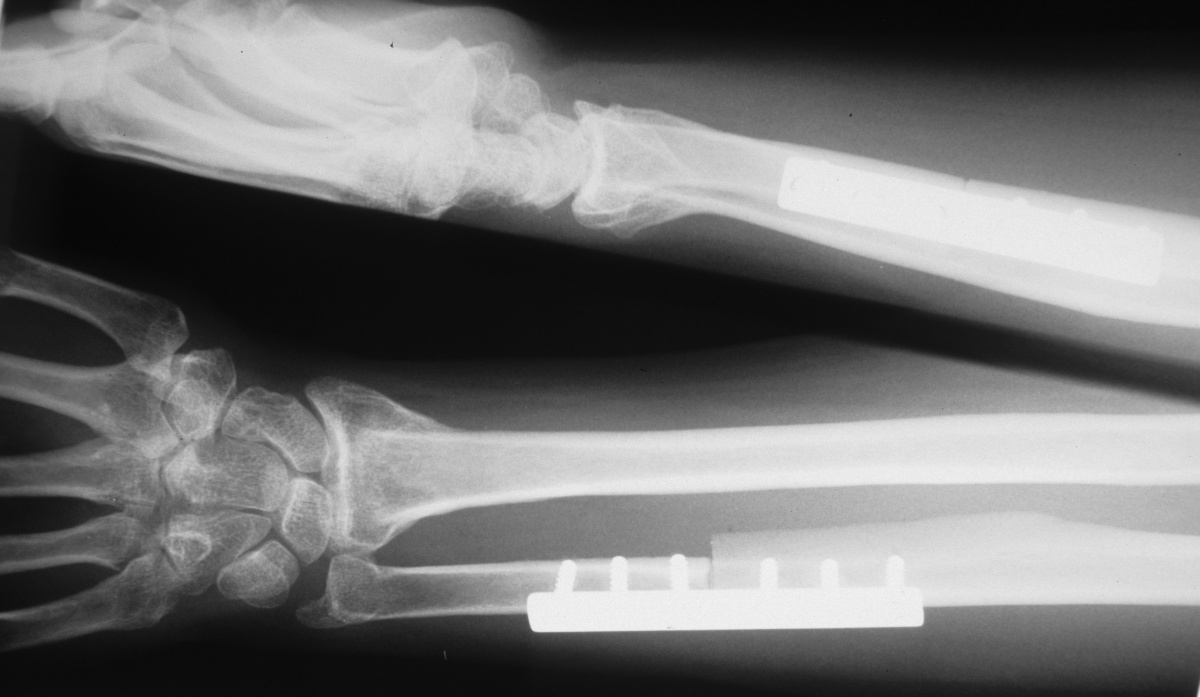

| After release of both

pronators from the radius and release of the distal half of the

interosseous membrane, passive supination was unchanged. A 60 degree

ulnar supination and 2 mm shortening osteotomy was performed,

with nearly 60 degrees improvement of supination intraoperatively. |

| Ulnar styloid position on a

forearm AP radiograph demonstrates the degree of rotation |